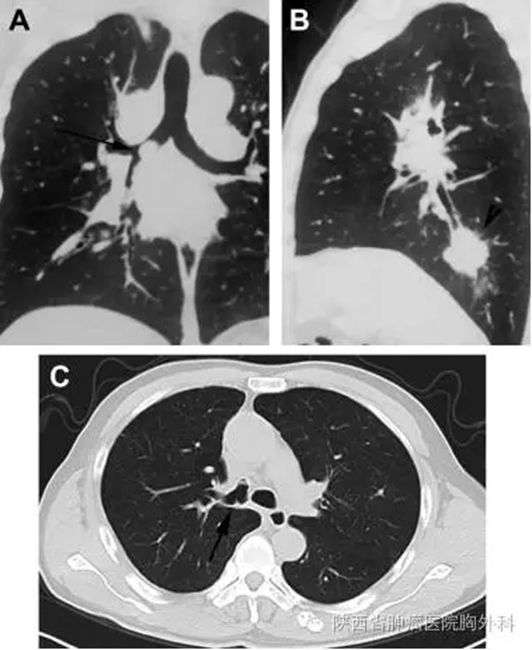

A.术前CT冠状图,箭头示右主支气管肿瘤;

B.术前CT矢状图,箭头示右下肺肿瘤;

C.术后2月CT横切图,保留的右肺上叶主支气管通气良好。